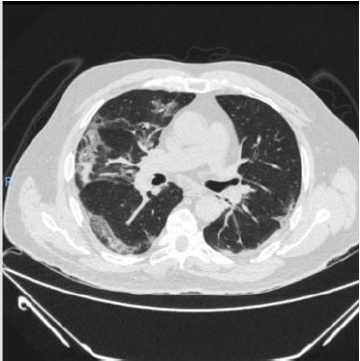

patient is identified with radiographic data from an unenhanced

chest computed tomography with multiple consolidative peripheral

opacities with ground-glass density in multiple lobes (Figures

1-6) with a peripheral distribution, which has been reported as a

common finding of SARS-CoV-2 pneumonia [6].